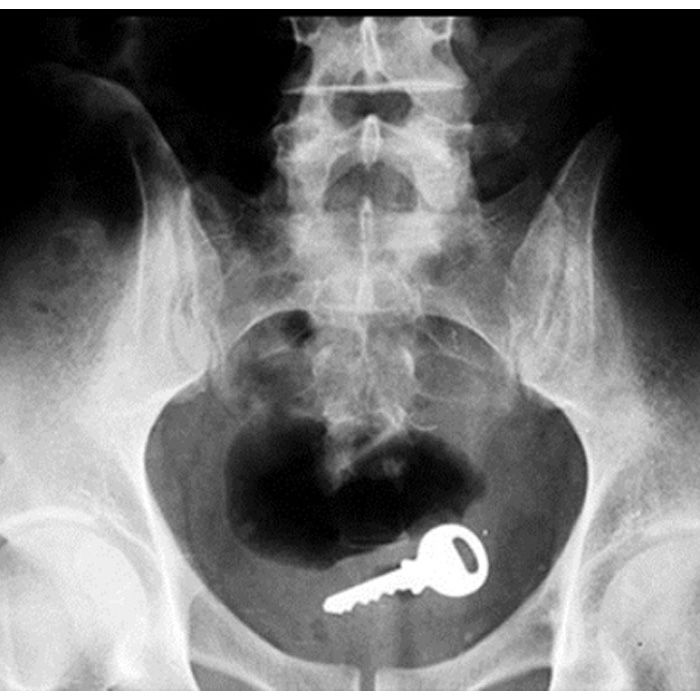

We could make a job about not being able to find the car keys … but would you really want them after this?